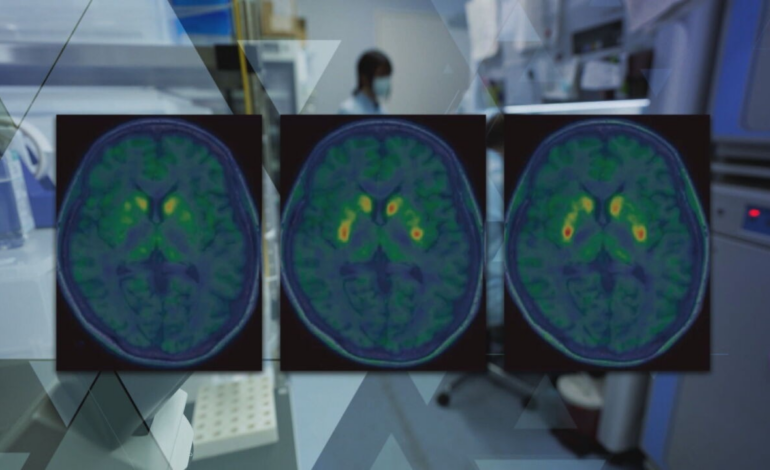

Terapia celular para Parkinson avança e tenta restaurar dopamina no cérebro: uma nova fronteira na medicina regenerativa

Uma das linhas mais promissoras da neurologia moderna está ganhando força: a terapia celular capaz de restaurar a produção de dopamina no cérebro de pacientes com Parkinson. Diferentemente dos tratamentos tradicionais — que apenas compensam a deficiência do neurotransmissor — essa abordagem busca atuar diretamente na causa da doença, abrindo caminho para uma possível mudança de paradigma no tratamento.

A doença de Parkinson é caracterizada pela morte progressiva de neurônios responsáveis pela produção de dopamina, um neurotransmissor essencial para o controle dos movimentos, além de influenciar memória, humor e motivação.

Como funciona a terapia celular no cérebro

A nova abordagem tenta resolver o problema na sua origem: substituir os neurônios perdidos por novas células capazes de produzir dopamina.

3. Produção de dopamina

Uma vez integradas, as células implantadas começam a produzir dopamina, ajudando a restaurar parcialmente o equilíbrio químico do cérebro.